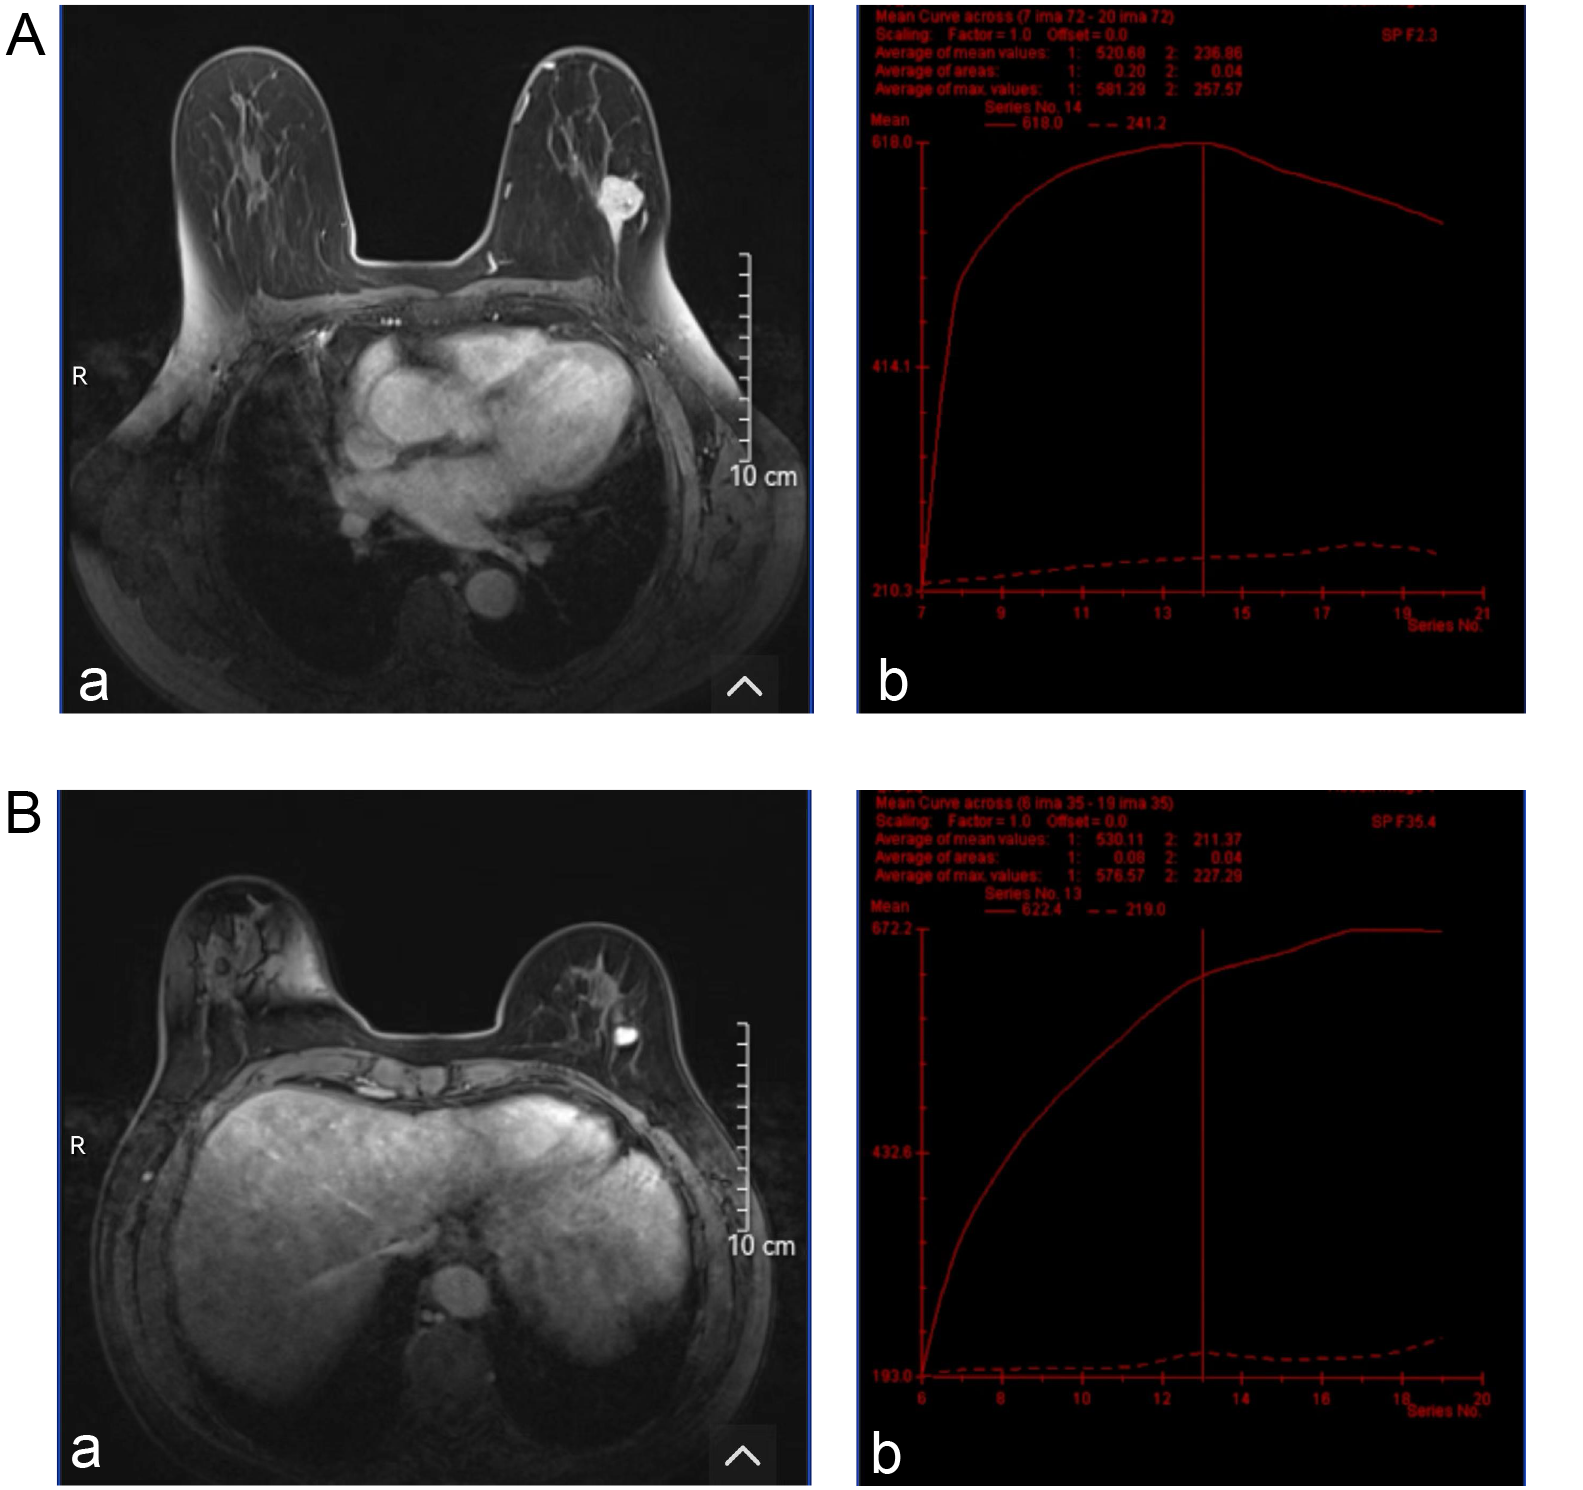

Magnetic resonance imaging evaluation of breast lesions

The shape and border differences of lesions evaluated with MRI were similar to the ultrasound features. More irregular shapes were found in malignant group compared to patients with the benign group (48.6% vs 23.4%; χ2 = 6.53, df = 1, p = 0.011) and more lesions with poor-defined borders were identified (51.4% vs 26.6%; χ2 = 6.12, df = 1, p = 0.013). The benign group demonstrated more homogeneous enhancement, whereas the malignant group showed greater heterogeneity (χ2 = 14.74, df = 1, p < 0.001). The average apparent diffusion coefficient (ADC) was 1.18 (0.95, 1.34) in the malignant group, which was higher than 0.80 (0.65, 0.91) in the benign group (z = 6.14, p < 0.001). Type III time-intensity curves (TICs) were more frequently observed in the malignant group compared to the benign group (51.4% vs 25%). Conversely, type I and type II TICs were more commonly seen in the benign group (42.2% vs 17.1% and 32.8% vs 31.4%, respectively). The differences were statistically significant (χ2 = 8.87, df = 2, p = 0.012) (Table 4). The typical MRI images and TIC from the malignant and benign groups are shown in Figure 3.

Magnetic resonance imaging evaluations of breast lesions presented in our study align with some of our ultrasound results, emphasizing the differences between benign and malignant lesions. Malignant lesions consistently exhibited irregular shapes (48.6% vs 23.4%, p = 0.011), poorly defined borders (51.4% vs 26.6%, p = 0.013) and heterogeneous enhancement patterns, consistent with findings in the literature.27, 28, 29 Notably, the higher average ADC values in malignant lesions (1.18 vs 0.80, p < 0.001) reaffirm their diagnostic significance.30 The distribution of TIC types further differentiated the lesions, with type III being predominant in malignancies, aligning with prior studies.31, 32 Meanwhile, MRI, recognized for its superior soft tissue contrast, demonstrated a sensitivity of 65.7%, specificity of 60.9% and an AUC of 0.633 in our study – values that are lower than those reported in previous literature.33, 34 This discrepancy may be attributed to our relatively small sample size and the inclusion of a substantial number of benign cases, suggesting that despite the lower performance in this study, MRI retains significant diagnostic value in detecting malignant breast lesions.